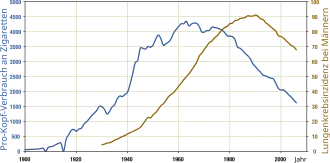

Historique

Le cancer du poumon n'était pas fréquent avant l'arrivée de la cigarette ; il n'a même pas été identifié comme une maladie distincte jusqu'en 1761[19]. Divers aspects du cancer du poumon ont été décrits avec plus de précisions en 1810[20]. Les tumeurs malignes du poumon ne représentaient qu'1 % de tous les cancers repérés en autopsie en 1878, mais étaient montés à 10–15 % au début du XXe siècle[21]. Le nombre de cas cités dans la littérature médicale mondiale ne s'élevait qu'à 374 en 1912[22], référence citée dans One hundred years of lung cancer[23], mais une revue des autopsies montre que l'incidence du cancer du poumon a augmenté de 0,3 % en 1852 à 5,66 % en 1952[24]. En Allemagne en 1929, le médecin Fritz Lickint reconnut le lien entre tabagisme et cancer du poumon[21], ce qui conduisit à une campagne antitabac agressive[25]. L'Étude des médecins britanniques, publiée dans les années 1950, était la première preuve épidémiologique solide du lien entre le cancer du poumon et le tabagisme[26]. De fait, en 1964 le chirurgien général des États-Unis[n 1] recommande aux fumeurs de s'arrêter de fumer[27].

Épidémiologie

Dans le monde, le cancer du poumon est le cancer le plus fréquent en termes tant d'incidence que de mortalité (1,35 million de nouveaux cas par an et 1,18 million de décès), avec les taux les plus élevés en Europe et en Amérique du Nord[37]. En France, sa prévalence varie fortement selon les régions : durant la seconde moitié du XXe siècle, chez les hommes, les régions à plus forte incidence étaient le Nord-Pas-de-Calais, la Lorraine et l'Alsace[38].

Fréquence

Le réseau français des registres des cancers (Francim) et l’Institut national de la santé et de la recherche médicale (Inserm) estiment le nombre total de nouveaux cas de cancers en France, en 2000, à 280 000, dont 58 % survenant chez les hommes. Pour la même année, le nombre de décès par cancer est estimé à 150 000 dont 61 % chez l’homme. Le cancer du poumon vient en 4e position pour son incidence (28 000 nouveaux cas) après le cancer du sein (42 000), de la prostate (40 000), et du colon et rectum (36 000) mais en première place pour sa mortalité. 23 152 cancers du poumon ont été diagnostiqués chez l’homme en 2000 et 4 591 chez la femme. Compte tenu de l’efficacité modeste des traitements, le cancer du poumon est la première cause de mort par cancer avec environ 27 000 décès en 2000, dont 23 000 chez l’homme et 4 500 chez la femme[39][source insuffisante]. Selon l'Assurance maladie, 14 237 nouveaux cas ont été détectés en France métropolitaine en 2002[réf. souhaitée].

En France, le nombre de nouveaux cas estimés en 2017 était de 49 000 : 32 000 hommes et 17 000 femmes[40].

Il fait partie des 9 cancers dont la fréquence a nettement augmenté de 1980 à 2005. Son incidence (23 937 nouveaux cas en 2005 en France) tend à augmenter chez l'homme jusqu'à la fin des années 1990, puis diminue sur la période 2000-2005, alors qu'elle augmente (de 4 % par an) chez les femmes sur la période la plus récente 2000-2005[41]. Le tabagisme est responsable dans plus de 90 % des cas, c'est de très loin le principal facteur de risque. Grâce à la prévention du tabagisme, dans les années 2000, l'épidémie de cancer du poumon commence à diminuer en France[42] ; tendance qui devrait se poursuivre car le taux de fumeurs masculins est passé de 70 % dans les années 1960[43] à 32 % au début des années 2010[44].

Cancer du poumon et tabagisme

Le segment de population développant un cancer du poumon le plus fréquemment est celui des plus de 50 ans ayant des antécédents de tabagisme. Le cancer du poumon est la forme de cancer arrivant en second rang en fréquence dans la plupart des pays occidentaux, et c'est la première cause de décès reliée au cancer.

Bien que le taux d'hommes mourants du cancer du poumon soit en baisse dans les pays occidentaux, il s'accroît chez les femmes, en raison de la montée du tabagisme dans ce groupe. L'évolution du lobby du tabac (Big Tobacco[n 2]) joue un rôle significatif dans la culture tabagique[46]. Les industriels du tabac ont concentré leurs efforts depuis les années 1970 vers le marché des femmes et jeunes filles, spécialement avec des cigarettes « light » ou « low-tar »[47].

À partir des années 1950, l'incidence de l'adénocarcinome du poumon a commencé à augmenter par rapport aux autres types de cancers[48]. Ceci est en partie dû à l'introduction des cigarettes à filtre : l'utilisation de filtres élimine les plus grosses particules de la fumée de tabac, réduisant ainsi les dépôts dans les plus grosses voies aériennes. Cependant, le fumeur doit aspirer plus fortement pour recevoir la même quantité de nicotine, ce qui accroît le dépôt de particules dans les voies les plus fines, d'où l'apparition de l'adénocarcinome[49].

Aux Etats-Unis, le cancer du poumon est la principale cause de décès du cancer chez l'homme et la femme, devant le cancer de la prostate et du sein, respectivement[50]. En France, le tabagisme est responsable dans plus de 90 % des cas. C'est de très loin le principal facteur de risque. En Belgique et au Canada, le tabac est responsable de 85 % des cancers du poumon[51],[52].

L'Europe de l'Est a le plus grand taux de mortalité par cancer du poumon parmi les hommes, tandis que l'Europe du Nord et les États-Unis ont la plus haute mortalité parmi les femmes. L'incidence du cancer du poumon est actuellement moindre dans les pays en développement[53]. Comme le tabagisme croît dans les pays en développement, on s'attend à avoir une croissance de l'incidence dans les années à venir, notamment en Chine[54] et en Inde[55].